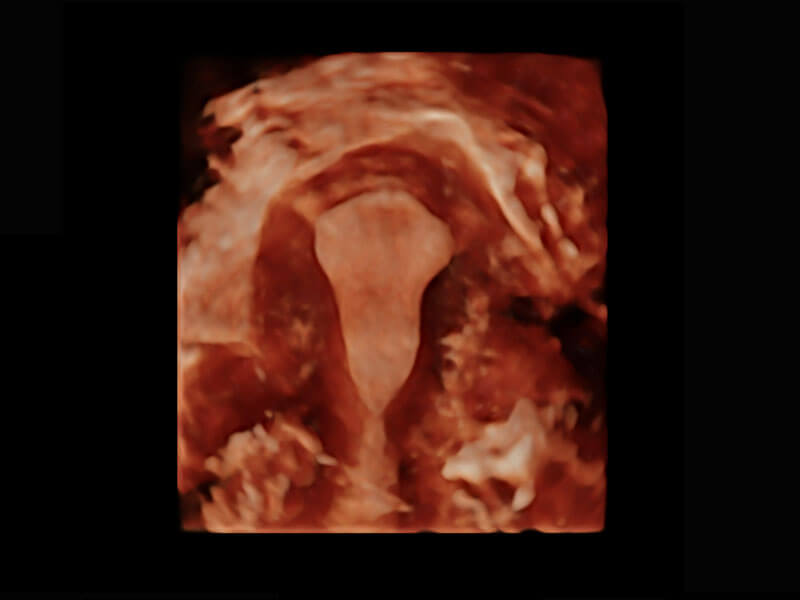

P60为盆底超声检查提供应用方案,多种腔内及腹部容积探头提供从二维、三维到四维的优异图像品质,实时快速三维容积数据获取,专业的测量工具包等人性化设计,为超声医生诊断提供有力保障。

Lev.Hiat A-r: 16.33 cm2

Lev.Hiat H-r: 53.70 mm

Lev.Hiat W-r: 43.96 mm

Lt-LUG-r: 24.16 mm

Rt-LUG-r: 19.94 mm

能够简化盆底检查的操作流程,可在二维模式及三维成像模式下实现一键自动提取出标准切面、自动识别当前切面、自动测量,提升盆底检查的高效性,同时也能让青年医生快捷的获得准确的检查结果。